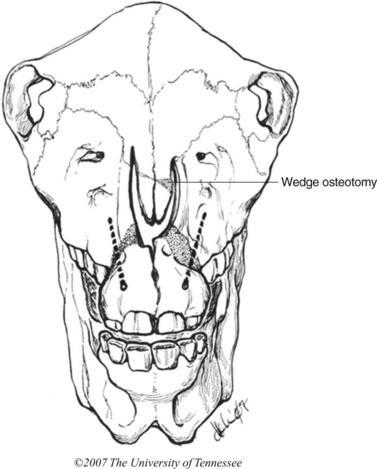

Surgical correction of dental malocclusion and dentofacial deformities in the horse has had limited application. The most severe types of deformities, such as wry nose, have been corrected successfully in a small number of horses by following the principles of orthognathic surgery.1013 Osteodistration surgical techniques have been employed to correct both wry nose and parrot mouth.14

Foals should be evaluated carefully for aspiration pneumonia and to rule out associated congenital defects. The degree of the deformity can be determined by oral radiographic examination, and computed tomography of the skull might be useful to confirm the position and degree of premaxillary/maxillary deviation and nasal obstruction (Fig. 19.15). Dental impressions of the upper and lower arcades from the premolars to the incisors can help the surgeon determine the amount of space created on the concave side of the premaxillae/maxillae when the deformity is corrected and the upper and lower incisor arcades are brought into proper occlusion (Fig. 19.16). Occlusal abnormalities of the premolars causing wear should be corrected prior to surgery. This involves re-establishing a normal occlusal angle on the premolar arcades and leveling the incisors (Fig. 19.17).

image

Fig. 19.17 (A) and (B) Twelve-year-old Thoroughbred mare with a wry nose. A ‘permanent’ tracheostomy as a yearling allowed the mare to breathe with no signs of respiratory distress. She had produced six normal foals while being bred to six different stallions. The uncorrected dental and facial deformity caused the mare difficulty with prehension and mastication. She had a severe shear mouth on the concave (right) arcades.